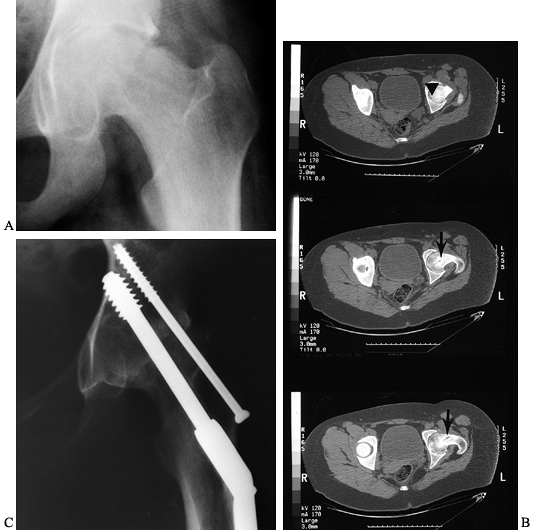

Figure 172.4. Technique of in situ single-screw fixation for SCFE. Preoperative AP (A) and frog-lateral (B)

radiographs of both hips in a 14-year-2-month-old boy. There is an SCFE of 40° on the right; the left hip is normal. A guide pin is placed onto the skin overlying the hip so that the pin is positioned in the center of the epiphysis and is perpendicular to the physis in both AP (C) and lateral (D) images. Skin lines are drawn to record the position of the guide pin on both the AP (E) and lateral (F) projections. The incision is marked at the intersection of the skin lines (G). After draping, multiple Kocher clamps are placed on the base of the drape to act as weights, which allows for movement of the image between AP (H) and lateral (I) images without violating surgical field sterility. The guide pin is advanced onto the anterolateral cortex of the femur so that the pin will enter the center of the epiphysis perpendicular to the physis. The guide pin is then advanced across the physis, and its tip is advanced no deeper than 5 mm from the subchondral bone [AP (J) and lateral (K) views]. The appropriate depth of the pin tip is checked using the lateral image. A cannulated screw is inserted in routine fashion after drilling and tapping the hole (L,M). Postoperative radiographs demonstrate ideal screw position in the center of the epiphysis perpendicular to the physis in both AP (N) and lateral (O) projections. |

-

Position the patient supine on a fracture

table, moving the image intensifier rather than the lower extremity.

Take care when transporting the patient onto the fracture table; no

reduction maneuvers are performed and forceful traction is not applied

to the lower extremity. I use the fracture table only as a positioning

device, allowing the involved limb to lie comfortably in its natural

position of rotation. -

Place the opposite limb into abduction

with the hip extended, and move the image intensifier into position

between the two lower extremities. -

Prior to surgical draping, confirm the ability to obtain adequate AP and cross-table lateral images.

Place a guide pin onto the skin overlying the proximal femur and obtain an AP image (48).

Position the pin in the center of the epiphysis and perpendicular to

the physis. Draw a line on the skin to record this guide pin position

in the AP projection. -

Draw a similar skin line for the lateral

image, again positioning the pin so that it is in the center of the

epiphysis and perpendicular to the physis.

relative to the femoral neck, and the guide pin in the lateral

projection angles from anterior to posterior. This is the opposite of

femoral neck fractures, where it angles from posterior to anterior.

Thus the two skin lines intersect on the anterolateral aspect of the

thigh, and as the slip becomes more severe, the intersection point

becomes more anterior. Because of the retroversion in the posteriorly

displaced epiphysis in SCFE, the osseous entry point of the guide pin

is on the anterior aspect of the femur. In mild SCFEs, it is often at

the anterior intertrochanteric line; in severe SCFEs, it moves up onto

the anterior femoral neck.

Prepare and drape the anterolateral

portion of the thigh. I prefer to use a transparent shower-curtain-type

of isolation drape with multiple Kocher clamps on the base of the drape

as weights; this allows movement of the image intensifier in both AP (Fig. 172.4H) and lateral (Fig. 172.4I) projections without violating surgical field sterility. -

Introduce the guide pin through the skin

at the intersection of the skin lines; it may be introduced through

either a stab wound or a small, 1–2 cm incision. -

Advance the guide pin onto the

anterolateral cortex of the femur, keeping the drill and guide pin

aligned according to the skin lines. Once the guide pin contacts the

femoral cortex, its point of entry and angular direction is confirmed

in both AP and lateral projections. -

When you are satisfied that the entry

point and direction of the guide pin are correct, carefully advance the

guide pin into the femoral neck, frequently checking the angle of entry

on both AP and lateral images. Ideally, there should only be one entry

point into the femoral cortex; extra holes act as stress risers and

increase the risk of postoperative fracture. Do not advance the guide

pin across the physis until you are certain that the pin will enter the

center of the epiphysis perpendicular to the physis in both AP and

lateral projections. -

After the pin has crossed the physis,

advance the tip to the proper depth (no closer than 5 mm from the

subchondral bone; any permanent pin position less than 5 mm from the

subchondral bone increases the risk of joint penetration). This depth

is determined on the lateral projection. Take care to ensure that the

pin is not in the superior quadrant of the femoral head, because this

position may jeopardize the epiphyseal blood supply. -

When the pin is in the appropriate

position, determine screw length by placing another guide wire of

identical length along the intraosseous guide wire and measuring the

difference. -

Insert a cannulated screw in routine fashion after drilling and tapping. The screw should be at least 6.5 mm in diameter.

While drilling and tapping, closely

monitor the guide pin to ensure that it (a) does not break, (b) does

not penetrate the joint and enter the abdominal cavity, or (c) does not

withdraw from the femoral neck. -

After inserting the screw, remove the

guide pin and confirm that the screw tip does not penetrate the joint.

This can be done by one of several techniques: (a) move the limb in

multiple directions in both AP and lateral views to confirm that it

does not penetrate the joint, (b) use the approach-withdraw phenomenon,

or (c) use intraoperative arthrography through the cannulated screw. My

approach is a variation of the first technique. I obtain images of the

hip every 10° to 15° while moving from a lateral to an AP projection,

ensuring that the screw tip is no closer than 5 mm to the subchondral

bone of the epiphysis. If it is closer than 5 mm, use a shorter screw. -

After confirmation of appropriate screw position and depth, close the incision.